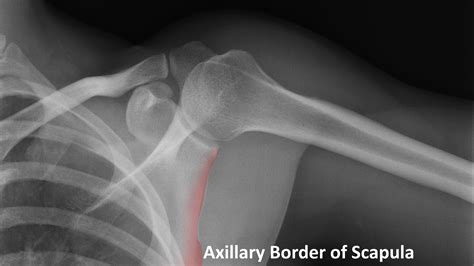

Understanding the significance of a shoulder X-ray normal result is crucial for both medical professionals and patients. A shoulder X-ray is a common diagnostic tool used to evaluate the bones, joints, and surrounding soft tissues of the shoulder. This imaging technique helps identify fractures, dislocations, arthritis, and other abnormalities. However, interpreting a shoulder X-ray normal result requires a thorough understanding of the anatomy and potential pathologies that can affect the shoulder.

The shoulder is a complex joint composed of several bones, muscles, and ligaments. The primary bones involved are the humerus (upper arm bone), scapula (shoulder blade), and clavicle (collarbone). The shoulder joint is a ball-and-socket joint, allowing for a wide range of motion. The rotator cuff, a group of muscles and tendons, plays a crucial role in stabilizing the shoulder and enabling movement.

A shoulder X-ray is a non-invasive imaging test that uses electromagnetic radiation to produce images of the shoulder joint and surrounding structures. This test is often the first step in diagnosing shoulder pain or injury. The X-ray can reveal fractures, dislocations, arthritis, and other bone abnormalities. However, it may not always show soft tissue injuries, such as tears in the rotator cuff or ligaments.